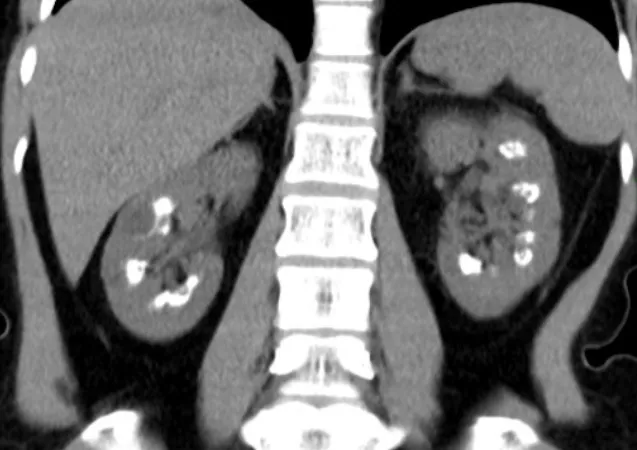

Uso do Tolvaptan na DRPAD: O Que falam nas Novas Diretrizes KDIGO 2025?

As novas diretrizes KDIGO para a Doença Renal Policística Autossômica Dominante (DRPAD) atualizam os critérios de elegibilidade para o uso de tolvaptana, com ênfase na estratificação do risco de progressão rápida. O documento reforça a individualização da terapia com base em subclassificação por imagem (Mayo Clinic) e função renal. A incorporação prática dessas recomendações pode otimizar o manejo e retardar a progressão da DRC nesses pacientes.

Valkercyo Feitosa